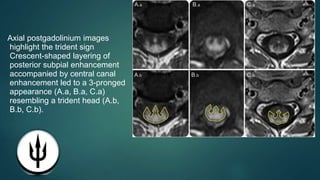

however, neurosarcoidosis may have distinguishing features including dorsal spinal cord

predominance, leptomeningeal enhancement, and the trident sign—crescentic posterior subpial

enhancement with subtle additional central canal enhancement

Sagittal MRI shows central canal enhancement in spinal cord sarcoidosis MRIs show longitudinally extensive T2

hyperintensity (A.a, B.a, C.a, D.a) with dorsal subpial enhancement (A.b, B.b, C.b; arrows) and central canal

enhancement (A.b, B.b, C.b, D.b; arrowheads).

Axial postgadolinium images

highlight the trident sign

Crescent-shaped layering of

posterior subpial enhancement

accompanied by central canal

enhancement led to a 3-pronged

appearance (A.a, B.a, C.a)

resembling a trident head (A.b,

B.b, C.b).